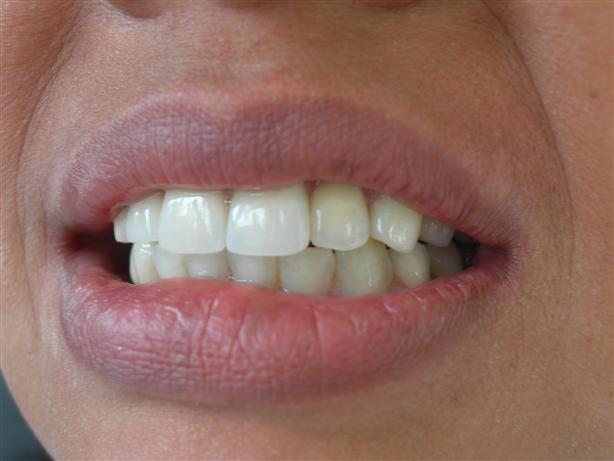

Vista frontal

Equilíbrio e harmonia facial reestabelecidos